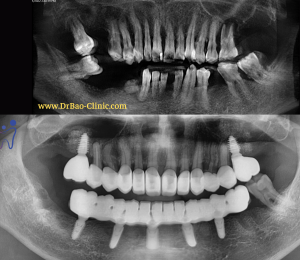

Phim X-Quang cho thấy có nhiều vùng nhiễm trùng ở hàm trên và dưới

Phục hình sau cùng chính thức sau 6 tháng cấy ghép Implant

X-Quang sau khi gắn phục hình chính thức

Tái khám sau 22 tháng mang phục hình sau cùng – nướu không viêm không sung. Phục hình ăn nhai tốt

Tái khám sau 22 tháng mang phục hình sau cùng – xương ổn định, không có hiện tượng viêm hay tiêu xương